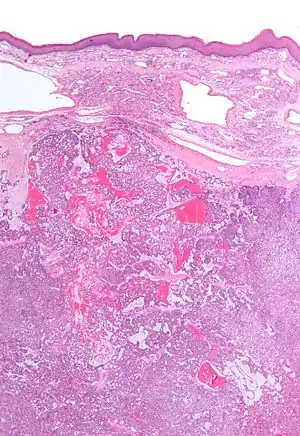

| Low magnification micrograph of a polymorphous low-grade adenocarcinoma, showing the typical variation of architectural arrangement. H&E stain. | |

PLGAs consist of a monomorphous cell population that has a varied histologic morphology.

Microscopically, its histology can be confused with an adenoid cystic carcinoma and a pleomorphic adenoma.

Polymorphous low-grade adenocarcinoma. H&E stain.

Micrograph of a polymorphous low-grade adenocarcinoma. H&E stain.